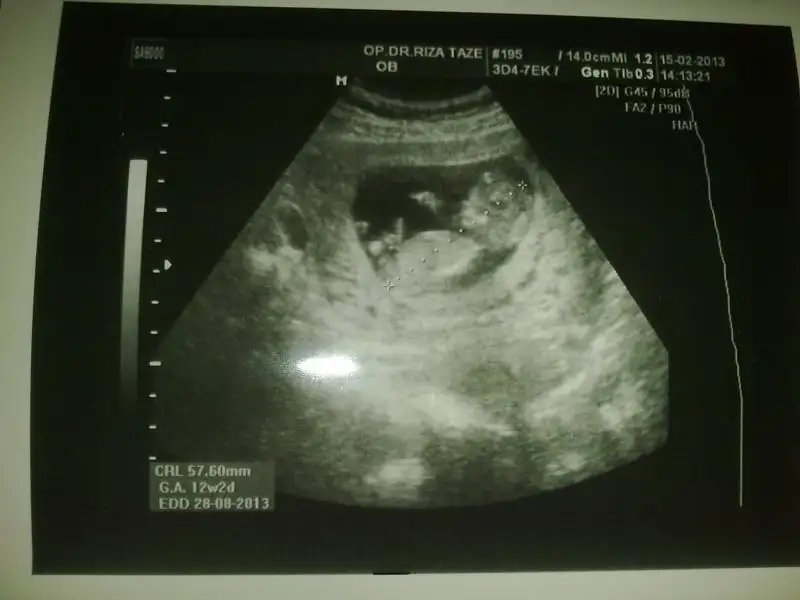

dr soylemeden siz gorun genital nub teorisi ( bebegin cinsiyeti)

burda bebegin nubu yok olmazda zaten ya kaybolup pipi olmustur yada kuku bu haftada bacak arasi lazim 12 13 varsa tekrar koyarmisin sana zahmettt

emin olmamakla birlikte paralell gordum sen daha net gorursun sence nasil paralelse kiz yani